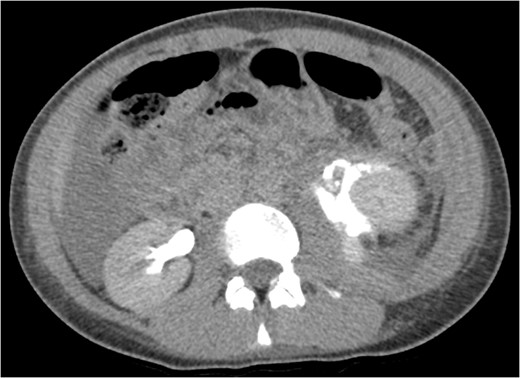

Coronal view reconstructions using maximum intensity projection, showing proximal ureteric leak of contrast.